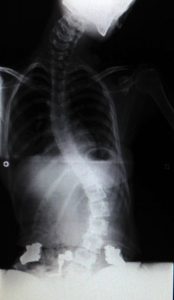

Radiografia frontal amb Spex

Amb Spex s’aconsegueix alinear l’escoliosi i fer desaparèixer el plec en el costat dret.